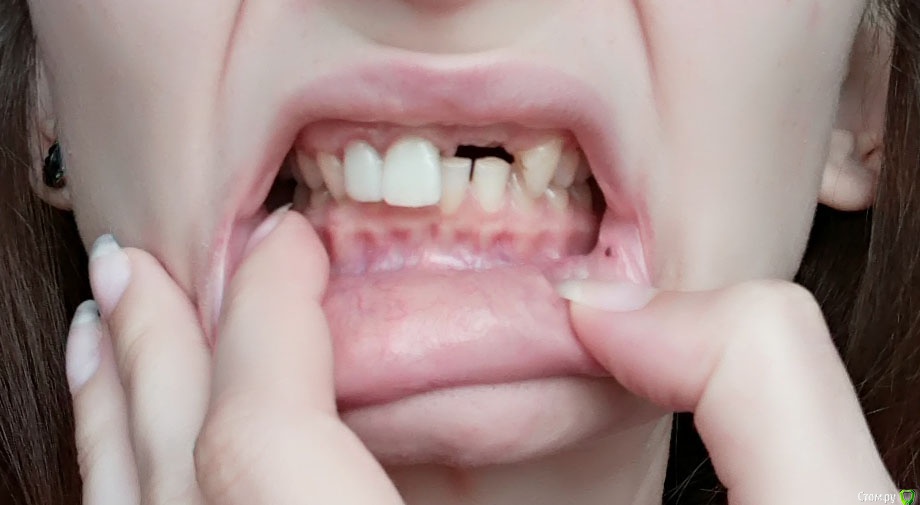

she-wo1f Опубликовано 16 сентября, 2017 Поделиться Опубликовано 16 сентября, 2017 Здравствуйте!Я планирую имплантацию 11, 12. В этой области уже была неудачная имплантация, подсадка кости и много других многолетних историй (не уверена, что подробности здесь нужны). 6ку снизу тоже буду имплантировать, но после передних.Ортопед, с которым консультировалась по поводу протезирования на будущих имплантах обратил мое внимание на неправильный прикус, и посоветовал проконсультироваться с ортодонтом, т.к. предположил возможность неправильной нагрузки на имплантированные резцы, и сопутствующие проблемы.Ортодонт по результатам осмотра и рентгена заключила, что исправление мне необходимо, и предложила брекеты на обе челюсти.Опыт знакомых и "людей из интернета" заставляет лишний раз задуматься действительно ли мне это необходимо.Меня не смущает эстетическая сторона вопроса и моя "неголливудская улыбка", хочется скорее привести зубы в умеренное состояние и забыть.Что бы вы посоветовали пациенту в моем случае?Достаточно ли брекетов в моем случае ? Читала, что в некоторых случаях требуется операция.Врач озвучила срок лечения брекетами - 1 год. Адекватная ли это цифра? Складывается впечатление, что в основном лечение занимает значительно больше времени.Возможны ли в моем случае альтернативы брекетам, например элайнеры? Ортодонт сказала одним из пунктов, что нужно выравнять направление верхних передних зубов, т.к. они сейчас "наружу". У меня оба резца под коронками... Есть ли смысл исправить направление коронковой части только переделав коронку и не исправлять это брекетами? Например, чтобы не травмировать лишний раз эти зубы.Есть ли какие-то риски при установке брекетов на коронки? Заранее благодарю за любые мнения! Ссылка на комментарий

she-wo1f Опубликовано 28 февраля, 2018 Автор Поделиться Опубликовано 28 февраля, 2018 (изменено) вновь доброго дня!вопрос в заголовке, пожалуй, не актуален. я решила, что хочу исправлять прикус. остается определиться со средствами. и, следовательно, такой вопрос:у меня передние верхние зубы полностью перекрывают нижние. + соприкасаются довольно плотно. в связи с этим, мне кажется, что брекеты на передних нижних зубах будут регулярно сдираться.похоже на реальную перспективу? + срезы КТhttps://drive.google.com/drive/folders/19I-XXNy0lLnsE3At-jksuy44a4sI9-w_?usp=sharing Изменено 28 февраля, 2018 пользователем she-wo1f Ссылка на комментарий

Brigita Опубликовано 2 марта, 2018 Поделиться Опубликовано 2 марта, 2018 Глубокий прикус не является прямым показаниям для элайнеров.В случаях, когда такой прикус мешает лечению делается разобщение. Есть несколько вариантов, какой именно нужен для пациента определяется врачом на приеме очно при обсуждении плана лечения. Ссылка на комментарий